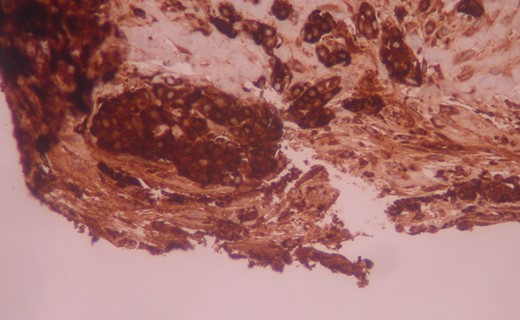

The patient was given a 7-day course of antibiotics prior to excision. The mass was then oncologically excised under local anesthesia. Histology identified infiltration of fatty abdominal wall tissue from acinic cells cancer and coagulative tumor necrosis, which led to the cystic formation of the lesion (Fig. 2). Immunohistochemistry revealed positive tumor cells for Keratin 8/18, trypsin and Chymotrypsin (Fig. 3). Further follow up scans revealed no metastasis, local recurrence or any other local growth.

The tumor cells are positive for chymotrypsin in immunohistochemistry. Immunostaining ×200.